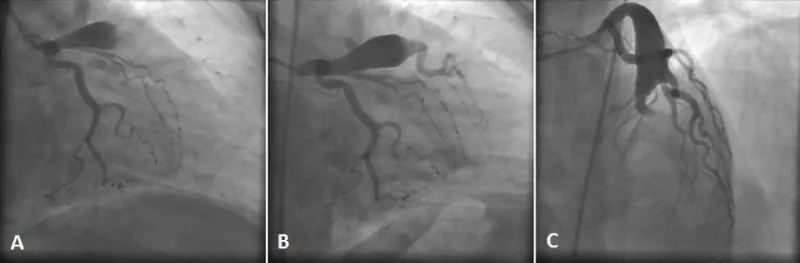

A 42 year old non-diabetic, non-hypertensive man was admitted to emergency department with chest pain continuing for 2 hours. Blood pressure and pulse rate were normal on physical examination of cardiovascular system. Electrocardiography revealed ST segment elevation in leads V1 to V4 (Figure 1). Echocardiography showed segmental wall motion abnormalities in anterior, anteroseptal and apical segments without any pericardial effusion. Laboratory analysis revealed elevated levels of Troponin I (39.6 ng/ml) and creatine kinase-myocardial band (24.5 ng/ml). He was transferred to coronary angiography unit for primary percutaneous intervention with the diagnosis of acute anteroseptal ST segment elevation myocardial infarction. Coronary angiography revealed a giant coronary artery aneurysm (20x40 mm in size) on the left anterior descending coronary artery (LAD). There was massive thrombus inside the aneurysm obstructing the distal coronary flow (Figure 2A). The circumflex and right coronary arteries were normal. Due to high thrombus burden and the lack of coronary blood flow distal to enurysm, thrombolytic therapy was administered with 10 mg intracoronary bolus and 90 mg intravenous infusion of tissue type plasminogen activator. A control coronary angiography after 12 hours showed partial lysis of the thrombus burden providing a TIMI III flow in the first diagonal artery. However there was TIMI 0-I flow in the distal LAD (Figure 2B and C). The co-decision of cardiology and cardiovascular surgery team was urgent surgery. However during the surgical preperation, the haemodynamic status of the patient failed. Echocardiography revealed that massive fibrinous pericardial effusion causing cardiac tamponade (Video 1). There was no sign of free wall rupture complicating acute myocardial infarction. Immediate pericardiosentesis yielded in 750 cc hemorrhagic fluid without any decrease in the pericardial effusion on echocardiography. Emergent chest opening by cardiovascular surgeon in the intensive care unit revealed the rupture of the giant coronary aneurysm. Soon after cardiac arrest occured before reconstruction of the LAD and the patient passed away after an unsatisfactory resusitation.

Figure 2: Coronary angiography revealed a giant coronary artery aneurysm (20x40 mm in size) on the left anterior descending coronary artery (LAD) with massive thrombus obstructing the distal coronary flow (A). Due to high thrombus burden and the lack of coronary blood flow distal to enurysm, thrombolytic therapy was performed with 10 mg intracoronary bolus and 90 mg intravenous infusion of tissue type plasminogen activator. A control coronary angiography 12 hours after thrombolytic therapy showed partial lysis of the thrombus burden providing a TIMI III flow in the first diagonal artery (B) and TIMI 0-I flow in the distal LAD (C).